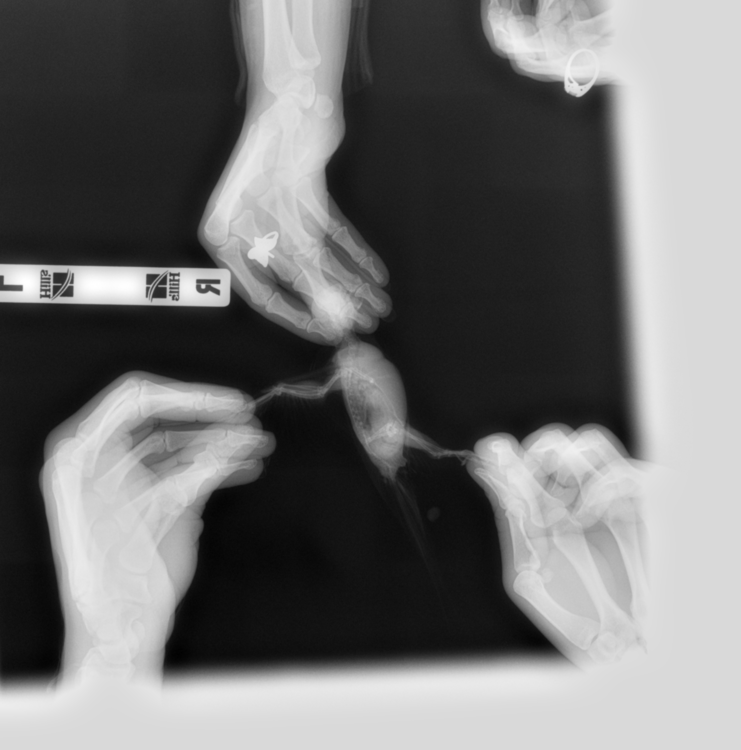

Venni Опубликовано 24 марта, 2019 Автор #117 Опубликовано 24 марта, 2019 (изменено) Всем здравствуйте. Сегодня были в вет.клиники. Врач брал мазок из зоба и клоаки- есть большое количество тонких, длинных палочек, но не мегабактерий, я ему даже фото с инете показывала мегабактерий под микроскопом, сказал не они, может и есть мегабактерии, но на фоне приёма противонрибковых лекарств, он их не видит, так же сделали рентген, рентген показал, что кишечник увеличен, печень в норме, полное описание скинет мне на почту вечером. По поводу бак.басева, у них только можно сделать на сальмонеллу, криптоспоридии и туберкулез, но этого мало, говорит вам в Воронеже нигде полный бак.пасев не сделает, делают только надо в Москву ехать, там лаборатории делают. Завтра буду звонить в обл.ветеринарную лабораторию, просить сделать бак.пасев., если нет, то хоть на эти 3 инфекции сдам, хотя толку мало. Как поддержать сейчас кишечник? Он ничего не назначил, говорит нужны анализы. Изменено 24 марта, 2019 пользователем Venni

KamaRo Опубликовано 24 марта, 2019 #118 Опубликовано 24 марта, 2019 @Venni выложите снимок рентгена, Зося его посмотрит и почитает. На счет мегабактерий и препаратов - болезнь неизлечимая, поэтому возбудитель может присутствовать в анализах. Как то удивительно, что обыватель ветеринару скидывает фото мегабактерий. Обычно вет.орнитологи, которые проводят и лабораторную диагностику, сами с атласами работают и консультируются у коллег более высокой квалификации. Нам вет.орнитолог даже группу возбудителей по микроскопии помета назвал, а посевом уже вид определяли и соответственно чувствительность к препарату. А как у собак/кошек возбудителей находят, ведь явно посевы делают? Областная вет.лаборатория как правило делает и бакпосев и микологический. На счет как поддержать кишечник, назначения уже дали - пробиотики, гепатопротекторы

Venni Опубликовано 25 марта, 2019 Автор #124 Опубликовано 25 марта, 2019 (изменено) Помёт на самом деле жёлто-зелёный, сейчас смотрю на фото очень светлый, хотя в телефоне цвет жёлто-зелёный. Выкладываю рентген. 9999_00014674.DCM 9999_00014673.DCM Изменено 25 марта, 2019 пользователем Venni

Venni Опубликовано 25 марта, 2019 Автор #125 Опубликовано 25 марта, 2019 (изменено) Сегодня сдали комлексный бак.посев с чувствительностью к антибиотикам, бактериофагам и антимикотическим препаратам. Пришлось вчера звонить в Москву в веттест, объяснила какой анализ мне нужен, сказали сделают, дали перечень вет.клиник в Воронеже с которыми они работают, где возьмут посев, правда долго делать будут 9-21 день, взависимости от роста. Изменено 25 марта, 2019 пользователем Venni

Venni Опубликовано 27 марта, 2019 Автор #134 Опубликовано 27 марта, 2019 @Zosia @Zosia Здравствуйте. Посмотрите пожалуйста наш рентген. На сколько пострадали органы от мегабактерий. 9999_00014673.DCM 9999_00014674.DCM

Venni Опубликовано 28 марта, 2019 Автор #135 Опубликовано 28 марта, 2019 @Zosia Добрый день. Посмотрите пожалуйста наш рентген. Файлы еле открыла. Извините, не разбираюсь в технике совсем.